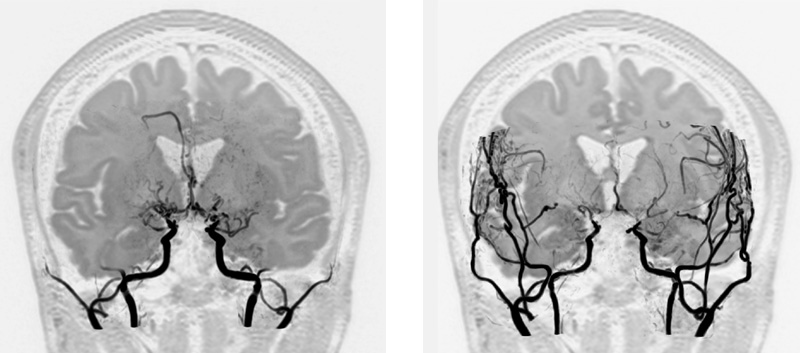

直接血行再建術と間接血行再建術を行った一例。

術後:外から発達した血管が脳を栄養していることがわかります。

術前:もやもや血管(赤い点線で囲まれた領域の黒いブツブツ)の発達を認めます。

術後:もやもや血管の退縮を認めます。